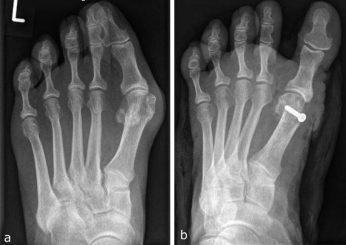

El hallux valgus es una deformidad de la parte delantera del pie, una subluxación de la articulación del primer metatarsiano (en lenguaje de la calle vendría a ser el dedo gordo del pie), que se desvía de su posición normal, lo cual es bastante común.

La desviación lateral del dedo gordo es claramente evidente cuando la persona está de pie y descalzo. Es

Es posible medir el ángulo entre el eje longitudinal del primer metatarsiano y la falange proximal del dedo gordo del pie. Aunque cada persona presenta un ángulo distinto se podría afirmar que un ángulo superior a 15° serían casos excepcionales. Lo normal es que no llegue hasta este ángulo y mucho menos que lo supere.

En la mayoría de los casos, aparte de este ángulo anómalo, se observa que el metatarsiano se hace más grande, aumenta la prominencia de la articulación.

La cirugía de hallux valgus es lo único que ofrece resultados más fiables, aunque no siempre permanentes. El estudio realizado por el Dr. Nikolaus Wülker junto a su compañero de trabajo el Dr. Falk Mittag demuestra que en el caso de la intervención quirúrgica aproximadamente el 85% de los pacientes que fueron operados habían resuelto el problema y el 10% notó una mejora de la situación. También hay que decir que el 5% restante no tuvo ninguna mejora. Pero recordad que muchas veces vuelve a aparecer de nuevo con el tiempo.